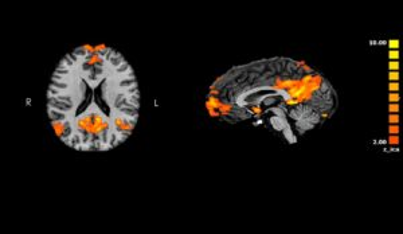

Our lab is dedicated to unraveling the psychological and neurobiological risk factors that contribute to the onset of mental health symptoms during periods of hormonal changes in women of reproductive age. We focus on critical stages, such as menstruation, pregnancy, and postpartum, when hormonal fluctuations can significantly impact mental health. Through our research, we seek to understand how early-life adversities, particularly exposure to childhood trauma, increase the vulnerability to mood and anxiety disorders during these times. Our approach is a multidisciplinary approach to research, integrating clinical assessments with advanced neuroimaging techniques, including functional and structural MRI and Diffusion Tensor Imaging (DTI). By exploring the interplay between psychological factors and brain patterns, we aim to identify biomarkers and psychosocial determinants that can predict mental health risks in reproductive-age women. This knowledge is crucial for the early identification and development of effective intervention for women at high risk of developing conditions like premenstrual symptoms and premenstrual dysphoric disorder (PMDD), perinatal mood and anxiety disorders and post-traumatic stress disorder (PTSD) in the perinatal period. We also lead large-scale longitudinal studies to investigate the effects of external stressors, such as the COVID-19 pandemic and other traumatic events, on pregnancy, maternal health and beahviour, and child development. Our lab's collaborative efforts extend across various specialties, ensuring a comprehensive approach to women’s mental health research. The laboratory is located within the outpatient clinics of the psychiatry division at Tel-Aviv Medical center - Ichilov. We work in proximity with the psychiatric services of women's health, Lis Maternity and Women's Hospital, and ELSC MRI Centers, and various laboratory around Israel specializing in early adversity and women's health, as well as international collaborations. to Trauma and Post-Traumatic Stress Disorder (PTSD) Our research project focuses on understanding the neurobiological imprint of exposure to trauma and the development of PTSD. Through large, multi-center clinical neuroimaging studies, we aim to characterize the behavioral and neuroimaging phenotypes of PTSD, leveraging advanced multimodal functional imaging techniques. These include functional MRI and Diffusion Tensor Imaging (DTI) to assess both functional and anatomical connectivity, as well as magnetoencephalography (MEG) for higher temporal resolution. Our research has revealed significant alterations in the default mode network’s anatomical and functional connectivity in PTSD patients, both from civilian and military-related trauma. Additionally, our studies have identified altered cerebral benzodiazepine receptor binding, shedding light on the neurochemical changes associated with PTSD. We also explore neural oscillations during the recollection of traumatic memories, contributing to a deeper understanding of the mechanisms underlying intrusive symptoms, hyper-arousal, and attention deficiencies in PTSD. The insights gained from this project are crucial for advancing the development of targeted interventions and therapies to alleviate the profound impact of trauma on the brain and mental health. of Premenstrual Dysphoric Disorder (PMDD) Our research delves into the psychological and neural underpinnings of PMDD, a severe mood disorder that significantly impacts many women’s lives during the luteal phase of their menstrual cycle. PMDD is regarded as an ‘in-vivo’ model for women with increased sensitivity to physiological fluctuations in sex-hormone levels, providing a unique lens through which we can study the broader implications of hormone-driven mood disorders. We investigate the difficulties in emotional regulation that are often observed in women with PMDD, exploring how these difficulties may contribute to the distressing symptoms experienced premenstrually. Our studies highlight how emotional regulation dysfunction plays a prominent role in premenstrual symptoms, particularly in women who have been exposed to childhood trauma. Additionally, we focused on identifying trait-related differences in neural network connectivity, particularly during tasks involving emotional processing, such as face-matching. The findings from this research have been presented at international conferences and published in high-ranking journals, further contributing to our understanding of PMDD. By examining these psychological and neural correlates, our research aims to inform more effective treatment strategies that target both the emotional processing and neural mechanisms underlying this disorder, ultimately improving the quality of life for those affected. During Pregnancy and Postpartum Our research project aims to identify the psychological and neural correlates of maternal childhood trauma to predict the risk of mood and anxiety symptoms during pregnancy and the postpartum period. This ongoing multidisciplinary longitudinal study combines psychosocial determinants and advanced multimodal imaging techniques, including functional MRI and diffusion tensor imaging, to assess women’s preconception vulnerabilities. By examining the influence of early-life adversity on maternal mental health, we aim to uncover key risk factors that could inform early interventions for pregnant and postpartum women. This project is particularly significant, as maternal mental health conditions such as depression and anxiety can impact both the mother and child’s well-being, potentially leading to long-term developmental consequences for the child. *Funded by the ISF Our research focuses on understanding the significant impact that adverse life events can have on women’s health, particularly mental well-being. We explore how factors such as cultural background, environmental stressors, and specific life stages—such as pregnancy and the postpartum period—contribute to an increased risk of mental health challenges. This work is particularly important as it sheds light on how these stressors can intensify during critical times in a woman’s life, leading to conditions like postpartum depression. By identifying the mechanisms through which these adverse experiences affect mental health, our research aims to inform the development of targeted interventions that can better support women in overcoming these challenges. As part of an international collaboration, we investigated the psychological implications of the COVID-19 pandemic among pregnant women. Lately, we have returned to investigate the same cohort to examine how the current events of the war in Israel influences the mothers and their offspring. *Funded by the ISF From The Press